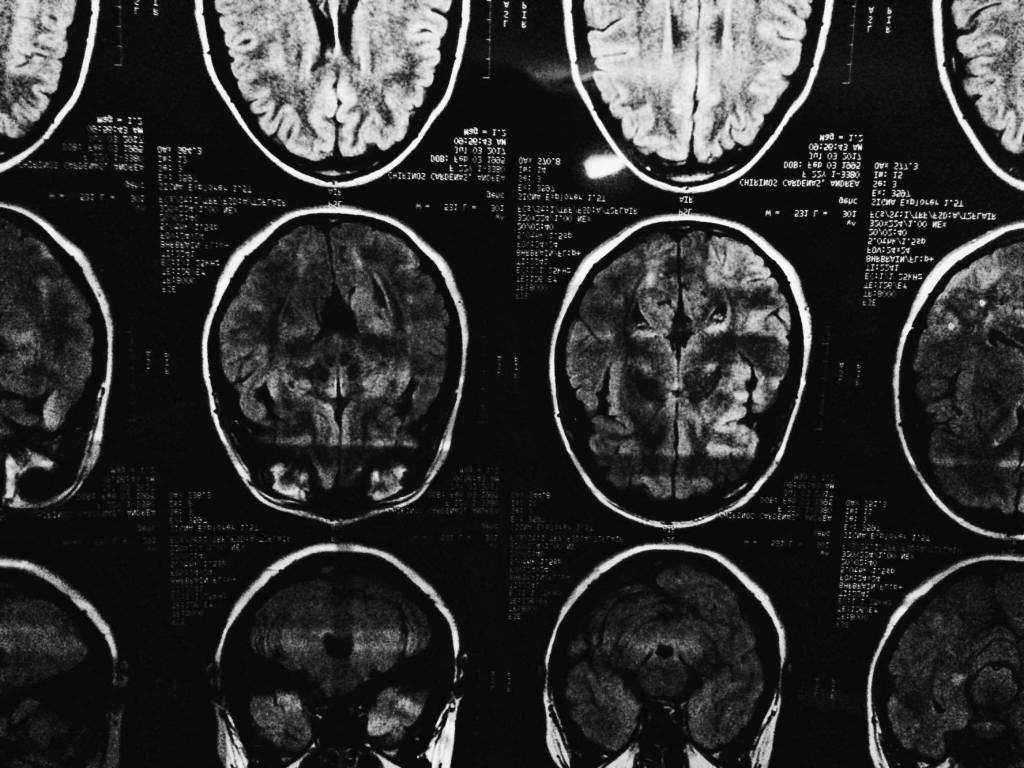

Mientras ella veía mis placas cerebrales.

Y yo solo pensaba «que el quiste sea benigno, que sea benigno porfavor»

Lo que había pasado, una hora antes de estar sentada en ese consultorio donde una señora gorda y muy buena gente revisaba mi cerebro mediante fotografías super raras que solo se pueden ver con una luz, rara también (no, no quiero buscar otro adjetivo para la cuestión), era que yo había leído los resultados antes que esta señora gorda y amable.

Quiste.

Pero salía quiste, quiste cerebral.

Quiste benigno.